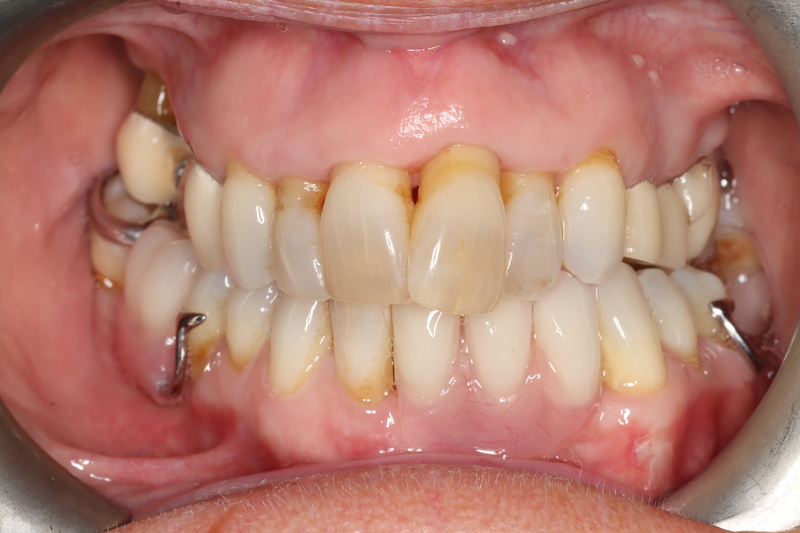

Case 14 – Multi Disciplinary

Remedial work from abroad.